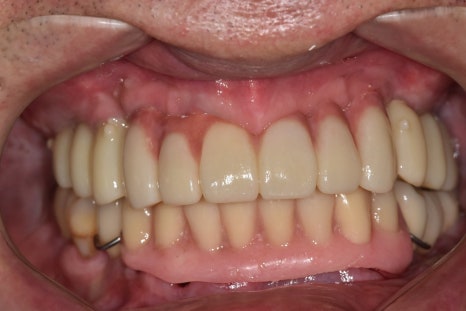

짠! 치아가 훨씬 자연스럽게 나왔습니다.

치아의 잇몸 쪽을 핑크포세린으로 덮어 자연스럽게 잇몸처럼 표현했습니다.